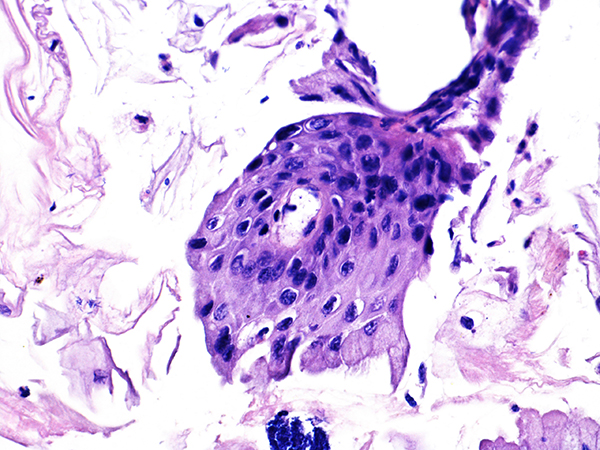

![]() Case 1

Area 1 - Soft Bx CIN 2 40x - High Power |